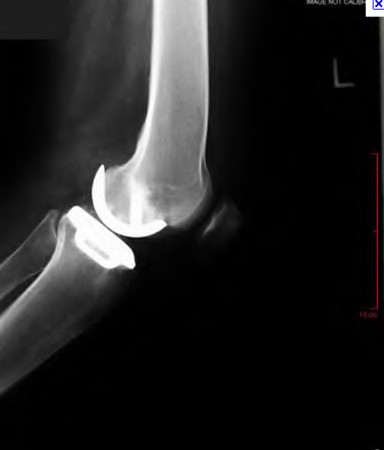

Question 18:

During a primary total knee arthroplasty (TKA), the surgeon evaluates the flexion and extension gaps. Utilizing spacer blocks, the surgeon notes that the extension gap is symmetric and perfectly balanced, but the flexion gap is excessively tight. Assuming an anterior referencing sizing guide was used, which of the following surgical adjustments is the most appropriate next step to balance the knee?

Correct Answer: Downsize the femoral component

Explanation:

When using an anterior referencing system, the anterior flange of all femoral components rests on the same cut surface. Downsizing the femoral component reduces its anteroposterior dimension by removing more bone from the posterior condyles. This specifically enlarges the flexion gap without altering the extension gap, thereby resolving an isolated tight flexion gap.